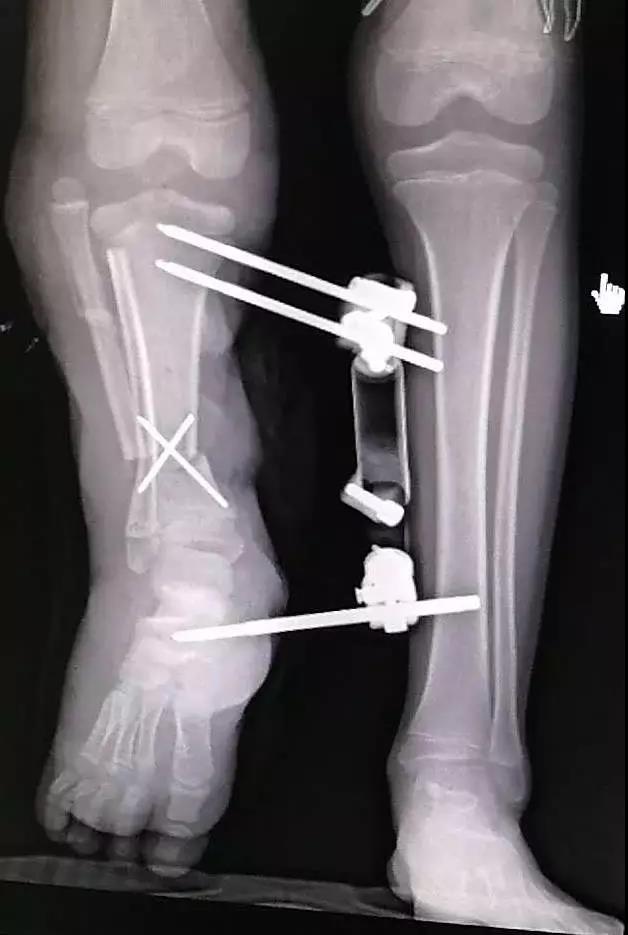

现代医疗技术

运动损伤及关节镜微创治疗技术、甲状腺腔镜技术、胃肠道肿瘤微创治疗技术、骨伤科脊柱微创技术、手显微外科技术、儿童骨折微创治疗技术、心血管介入诊疗技术、夫精人工授精技术、介入诊疗技术......